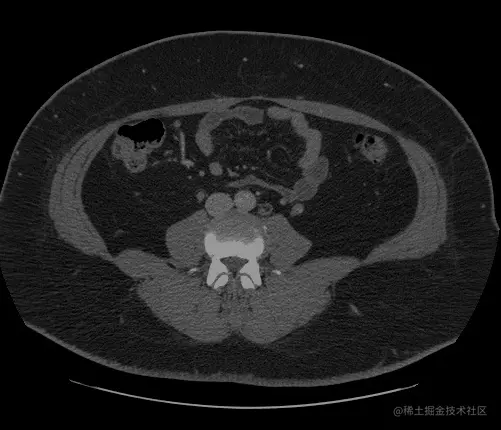

随着人工智能的崛起,将神经网络与医疗诊断结合也成为研究热点,智能医疗研究逐渐成熟。在智能医疗领域,语义分割主要应用于肿瘤图像分割,龋齿诊断等。(下图分别是龋齿诊断,头部CT扫描紧急护理诊断辅助和肺癌诊断辅助) 在这里插入图片描述 在这里插入图片描述